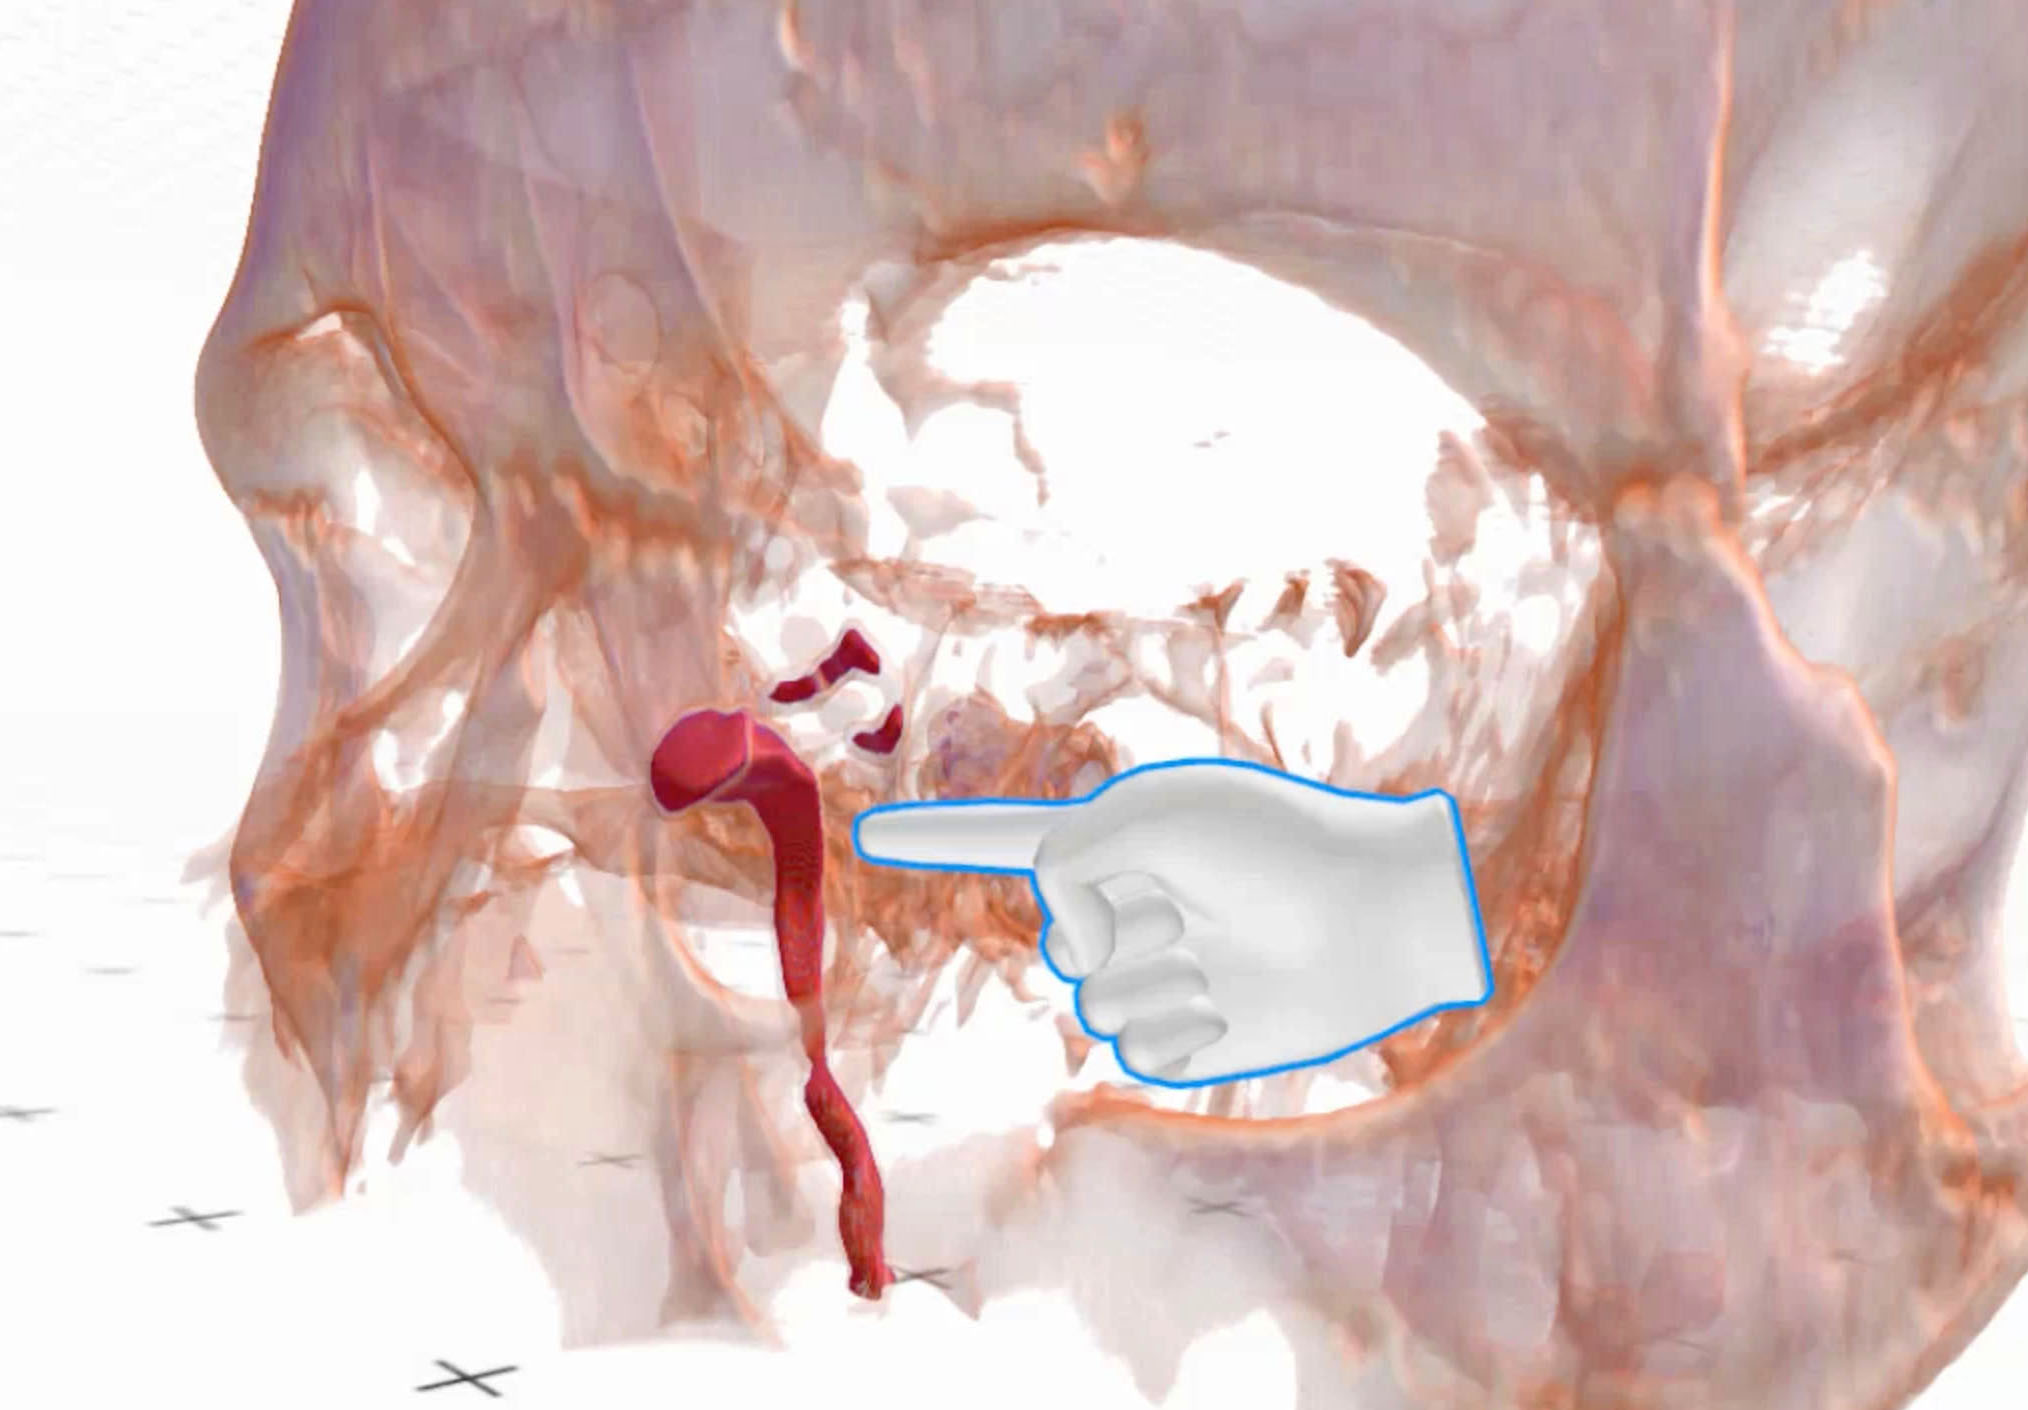

A groundbreaking approach to tackling complex lacrimal obstructions.

Read more User story

Endoscopic dacryocystorhinostomy in posttraumatic nasolacrimal duct obstruction.